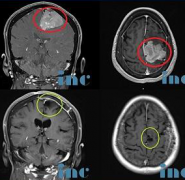

【较大脑膜瘤手术案例】故事源于一封字里行间充满了希望与感激的感谢信,写给INC之德国巴特朗菲教授,来自一个被较大脑膜瘤折磨导致肢体无力多年的...

颅内较大脑膜瘤案例:这是一封来自一名大脑镰旁脑膜瘤患者的感谢信。在网络信息这么发达的时代,这位可爱的阿姨仍然用自己较朴实的方式表达着自己...

【脑瘤治疗案例汇总】INC曾接诊的这四个真实的疑难脑瘤手术案例或许正能解答大家的这些疑问。就这些案例患者而言,术前教授都曾给到他们明确的可以...